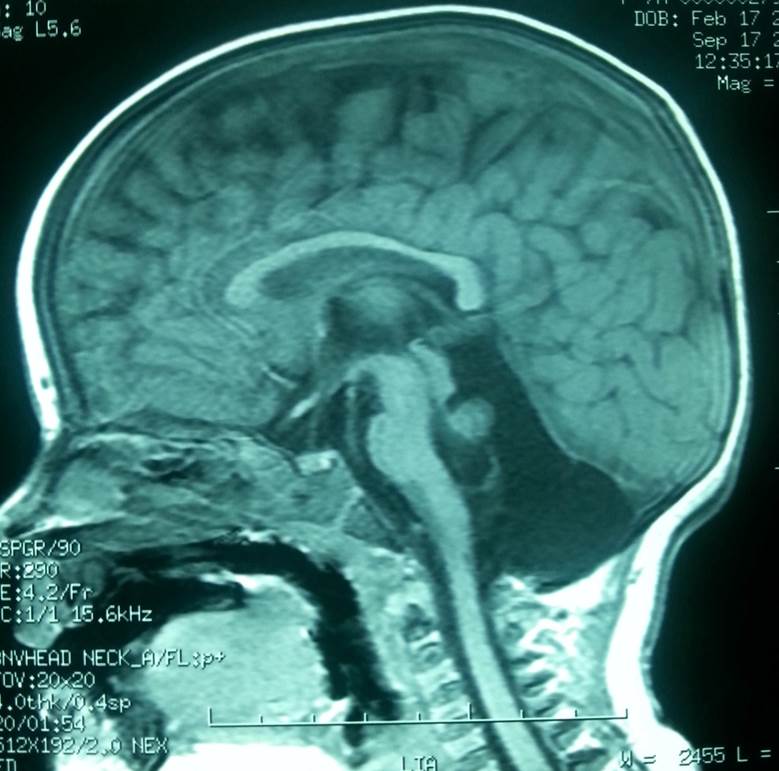

Presentamos el caso de una niña de 9 años, tercera hija de padres sanos no consanguíneos. Durante el segundo mes de embarazo su madre padeció una trombosis venosa profunda que requirió tratamiento con heparina y medias de compresión. Nacida a término con peso adecuado, no necesitó reanimación neonatal. Se alimentó con lactancia materna exclusiva hasta los 6 meses. A los 4 meses de edad, en una revisión rutinaria en el centro de salud, se detectó un nistagmus horizontal, estrabismo ocular de difícil exploración debido a su corta edad y una leve hipotonía del cuello y tronco, por lo que fue derivada a neurología infantil del hospital de referencia. Allí se realizó una resonancia nuclear magnética (RNM), detectándose una hipoplasia grave parcial del cerebelo, con ausencia total del vermis (Figuras 1 y 2). El sistema ventricular supratentorial y el parénquima cerebral no presentaban alteraciones. Se pronosticó una gran dificultad para la marcha debido a la grave afectación cerebelosa. Se recomendó estimulación precoz y rehabilitación, que la niña ha realizado de forma pública y privada con gran implicación familiar. Adquirió la marcha y el habla tardíamente, alrededor de los 3,5 años.

La RNM se repitió a los 9 años y no presenta diferencias con la anterior. El estudio genético ha sido realizado recientemente, mediante estudio de hibridación genómica comparada con “array”, se detecta una ganancia de material genómico en la región 15q11.2, con duplicación del fragmento BP1-BP2 de un tamaño aproximado de 396 kilobases, heredada de su padre (que no presenta ninguna manifestación clínica).